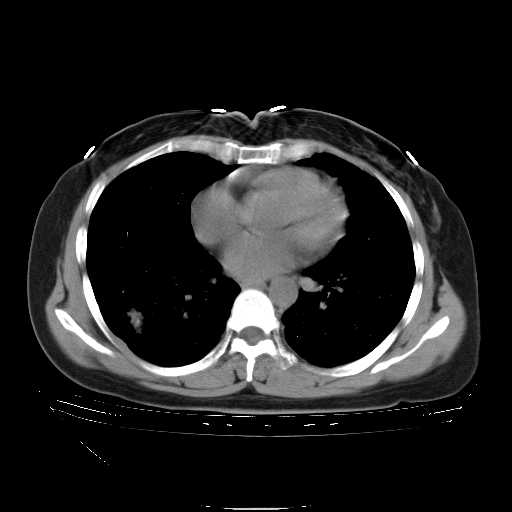

f50,肺ca治疗后,做过穿刺,确诊是肺ca,大家看看这是去年12月做的